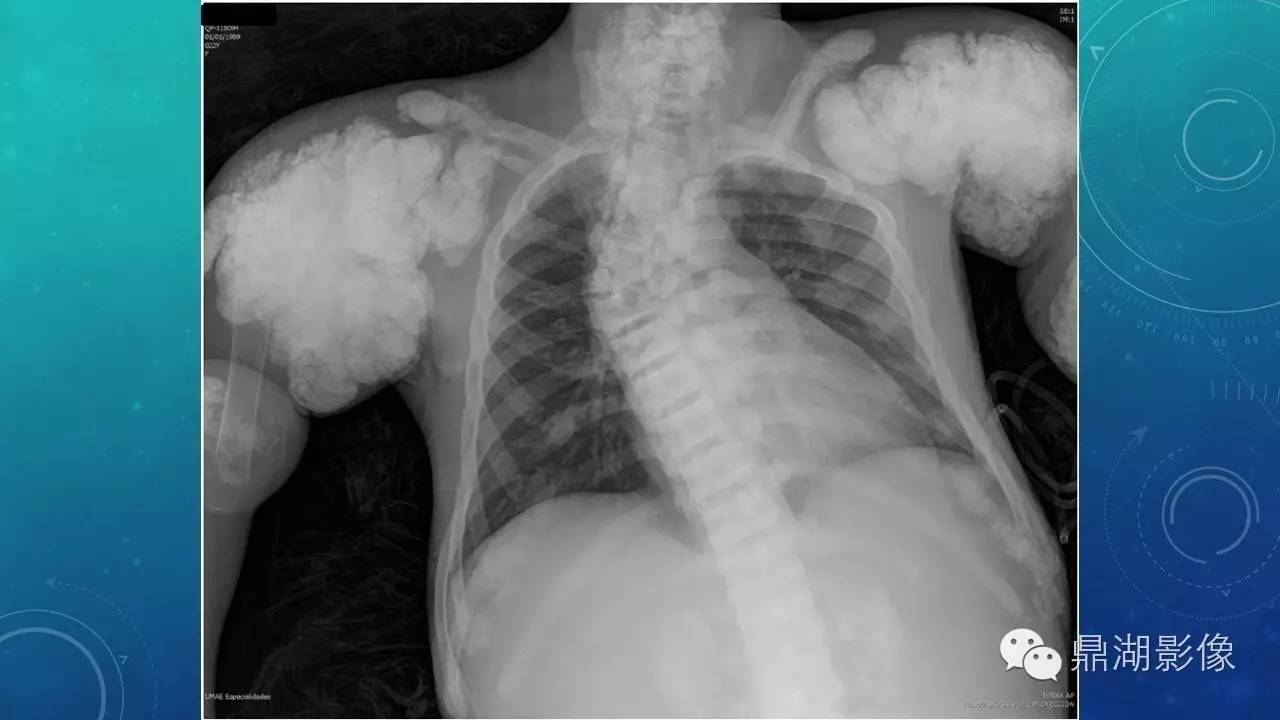

软组织钙化(的鉴别)